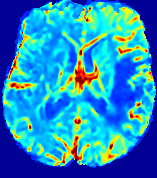

LesionRefer to captionRefer to captionRefer to captionRefer to captionRefer to captionRefer to caption𝐕rgbsubscript𝐕𝑟𝑔𝑏{\bf{V}}_{rgb}Refer to captionRefer to captionRefer to captionRefer to captionRefer to captionRefer to caption𝐕2subscriptnorm𝐕2{\|\bf{V}}\|_{2}Refer to captionRefer to captionRefer to captionRefer to captionRefer to captionRefer to captionRefer to caption3.53.53.52.82.82.82.12.12.11.41.41.40.70.70.70.00.00.0(mm/s)𝑚𝑚𝑠(mm/s)D𝐷DRefer to captionRefer to captionRefer to captionRefer to captionRefer to captionRefer to captionRefer to caption0.0200.0200.0200.0160.0160.0160.0120.0120.0120.0080.0080.0080.0040.0040.0040.0000.0000.000(mm2/s)𝑚superscript𝑚2𝑠(mm^{2}/s)Slice #1Slice #2Slice #3Slice #4Slice #5Slice #6

Figure 3: PIANO feature maps for one stroke patient, where the lesion is located in the left hemisphere. Top row: segmented stroke lesion region (white) on different slices, obtained from ISLES 2017. The corresponding slices for the PIANO feature maps are shown in the following rows.

For a better insight into an estimated velocity field 𝐕𝐕{\bf{V}} and diffusion field 𝐃𝐃{\bf{D}}, we compute the following maps: (1) 𝐕rgbsubscript𝐕𝑟𝑔𝑏{\bf{V}}_{rgb}: Color-coded orientation map of 𝐕=(Vx,Vy,Vz)T𝐕superscriptsuperscript𝑉𝑥superscript𝑉𝑦superscript𝑉𝑧𝑇{\bf{V}}=(V^{x},V^{y},V^{z})^{T}, obtained by normalizing 𝐕𝐕{\bf{V}} to unit length and mapping its 3 components to red, green, blue respectively; (2) 𝐕2subscriptnorm𝐕2\|{\bf{V}}\|_{2}: 222 norm of 𝐕𝐕{\bf{V}}; (3) D𝐷D: scalar field in Eq. 5.

Fig. 3 and Fig. 4 show the PIANO feature maps estimated from two ISLES 2017 patients: all are highly consistent with the lesion in both cases. Details of the blood flow trajectories are revealed in 𝐕rgbsubscript𝐕𝑟𝑔𝑏{\bf{V}}_{rgb} by the ridged patterns and the sharp changes of colors in the unaffected (right) hemisphere, while the flat patterns appearing within the lesion provide little directional information about the velocity and indicate low velocity magnitudes. Velocity magnitudes are more directly visualized via 𝐕2subscriptnorm𝐕2\|{\bf{V}}\|_{2}, from which one can easily locate the lesion where 𝐕2subscriptnorm𝐕2\|{\bf{V}}\|_{2} is low. D𝐷D also indicates lower diffusion values in the lesion, though with less contrast potentially due to the fact that it captures the accumulated effect of CA diffusion at the voxel-level.